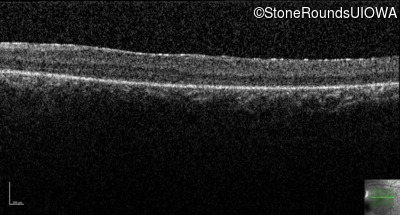

Age at visit: 22 years

Age at visit: 24 years

Age at visit: 26 years